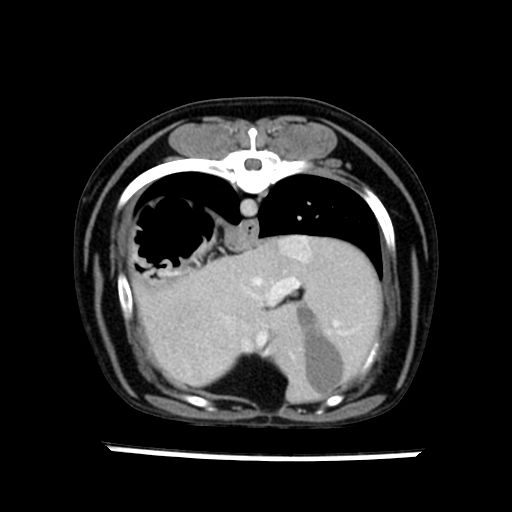

prescritto esame TAC

sequenza immagini limitata al fegato reni e surreni

sospetto adenoma ipofisario vs. meno probabilmente meningioma della base; intertiziopatia polmonare; lesione espansiva epatica, verosimilmente del lobo laterale sinistro, di sospetta natura neoplastica; lesioni spleniche di natura da definire; iperplasia/ipertrofia delle ghiandole surrenali, bilateralmente; vertebra di transizione del rachide toracico; tenosinovite cronica del muscolo bicipite brachiale di destra.

- l’esame tac e’ stato eseguito circa quattro mesi dopo la prima ecografia che non aveva messo in evidenza aumento del volume surrenalico (vedi immagini) ma solo la lesione epatica, la presenza di PU PD aveva portato ad un controllo per l’ ipercorticosurrenalismo confermato dal test act , in questo caso, si deduce che i sintomi di ipercorticosurrenalismo legati all’adenoma sono comparsi prima delle modificazioni surrenaliche, quindi in caso di sospetto ,a mio avviso e’ buona norma eseguire prima il test di stimolazione e dopo L’ECOGRAFIA per tentare una classificazione eziopatogenetica . La Tac si e’ quindi dimostrata molto valida in sensibilita’ e specificita’ riguardo la patologia surrenalica in quanto in grado di vedere o fortemente sospettare (ovviamente meno sensibile della RM) un piccolo adenoma ipofisario e le alterazioni morfovolumetriche della surrenale.

- Nessuna informazione diversa per quello che riguarda l’esame ecografico del fegato e la presa del contrasto si confermano le lesioni individuate e l’ipoenanchement in fase portale.

- la total body permette di escludere metastasi e di avvicinarsi all’interventistica

la tac dopo 7 mesi permette misure tridimensionali 5,2 x 9,2 x 4,5 cm (forma piu’ allungata )